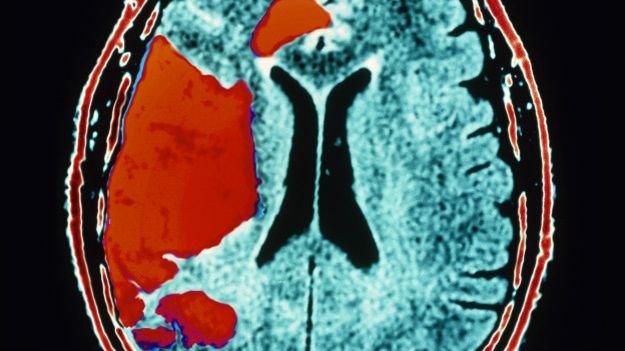

beyin felçÜniversite eğitimi görmüş kişilerin yaşadığı unutkanlıkların, felç habercisi olabileceği belirtildi. Hollanda’da yapılan ve Stroke dergisinde yayımlanan araştırmaya göre, yüksek eğitimli insanların felç geçirmesi olasılığı, daha düşük eğitimlilere kıyasla % 39 daha fazla.

Arfan Ikram, bu tip vakalarda bellek zorunlarının önemli bir uyarı olabileceğini ve bu insanlardaki gelişmelere özellikle dikkat edilmesi gerektiğini kaydediyor. Felç, beyne oksijen ve besleyici öğeler taşıyan kan damarlarından birinin kan pıhtısıyla tıkanması veya patlaması ile meydana geliyor. Bu olduğunda, beynin bir kısmı gerek duyduğu kan ve oksijeni alamıyor ve beyin hücreleri ölüyor.